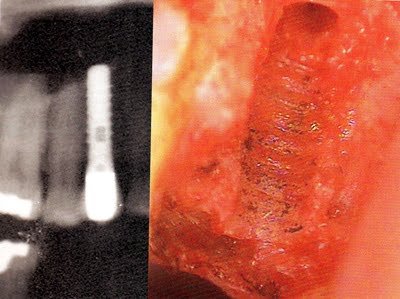

Certains professionnels tiennent compte de cette spécificité individuelle et effectuent des recherches en ce sens. À Munich, un dentiste fait autorité : Dr Lechner, un homme aujourd’hui sexagénaire. Depuis quelques années déjà, il tente d’avertir ses congénères du danger des dents dévitalisées, responsables de bien des maladies auto-immunes et de nombreuses maladies dégénératives. Pour lui, c’est sans appel : le corps ne supporte aucune exposition prolongée aux métaux, quel que soit le métal.

Pour les implants et les couronnes, il utilise un composite spécial qu’il a mis au point après des années d’expérimentation. Je suis allé dans son institut et je l’ai testé. J’avoue que c’est incroyable. Le corps le tolère particulièrement bien, si ce n’est parfaitement. J’ai vu qu’il s’était entouré d’une équipe spécialisée dans l’aspect énergétique de l’être humain et de l’environnement. Cela expliquerait la parfaite concordance de ce matériau avec l’organisme.